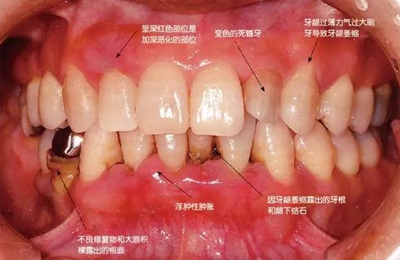

患有牙周病的牙周組織是什么樣的呢?

牙周炎的患者主要有三種臨床癥狀,分別是牙齦炎癥、真性牙周袋的形成、牙槽骨吸收。牙齦呈浮腫性或纖維性腫脹、喪失對(duì)牙面的附著形成牙周袋。有時(shí)炎癥持續(xù)時(shí)間太長(zhǎng),會(huì)在接受牙周病治療后牙齦萎縮,牙根暴露。

在牙周袋內(nèi)形成混有血液的黑色齦下牙石。

患有牙周病的牙周組織的臨床照片

56歲牙周炎男性的臨床照片

正在服用高血壓藥中的56歲男性。菌斑控制得不好。通過(guò)牙周探診,全頜有4~6mm的牙周袋,在X光片中可以看到全頜中度牙槽骨吸收,磨牙處一個(gè)地方是重度牙槽骨吸收。通過(guò)比較牙周病進(jìn)展?fàn)顟B(tài),邊緣部有大范圍浮腫(發(fā)紅、腫脹),和纖維性肥厚。這也可能是服用中的降壓藥的副作用導(dǎo)致的。因?yàn)檠例l、牙槽骨比較厚,牙齦呈架子狀。